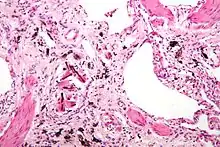

| Micrograph of asbestosis (with ferruginous bodies), a type of pneumoconiosis. H&E stain. | |